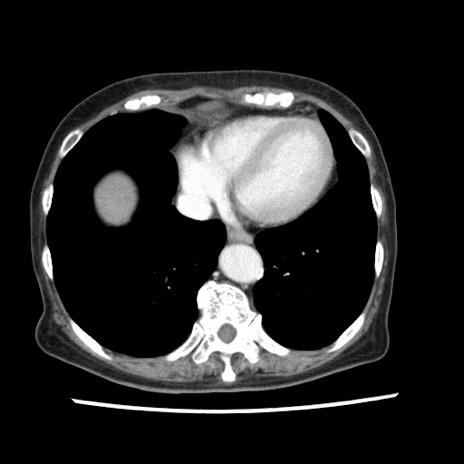

症例1(横断像)

症例

【症例】80歳代女性

【主訴】腹痛

【現病歴】8時間前から腹痛あり来院。

【既往歴】糖尿病、脂質異常症、子宮体癌にて子宮全摘術

【身体所見】意識清明・会話良好だが腹痛で苦悶様、全腹部にわたって反跳痛と圧痛あり

【データ】WBC 13600、CRP 0.14、LDH 224、CK 90